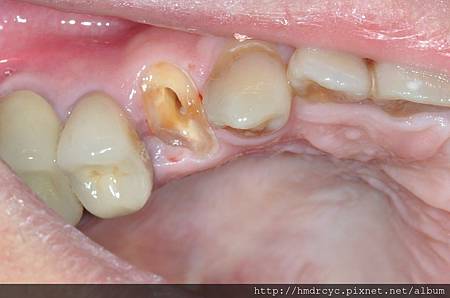

當牙齒因為蛀牙或斷裂

導致本身剩下的結構不足

套假牙時沒有足夠支撐

容易造成假牙脫落或剩下牙齒斷裂

因為蛀牙造成牙齒缺損嚴重